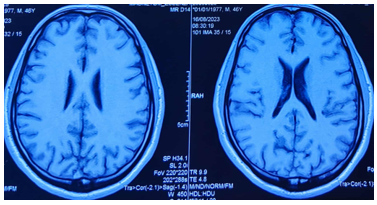

Bệnh nhân được chụp Cộng hưởng từ sọ não: Chưa phát hiện tổn thương

Hình 5: Hình ảnh chụp cộng hưởng từ sọ não: Không phát hiện tổn thương